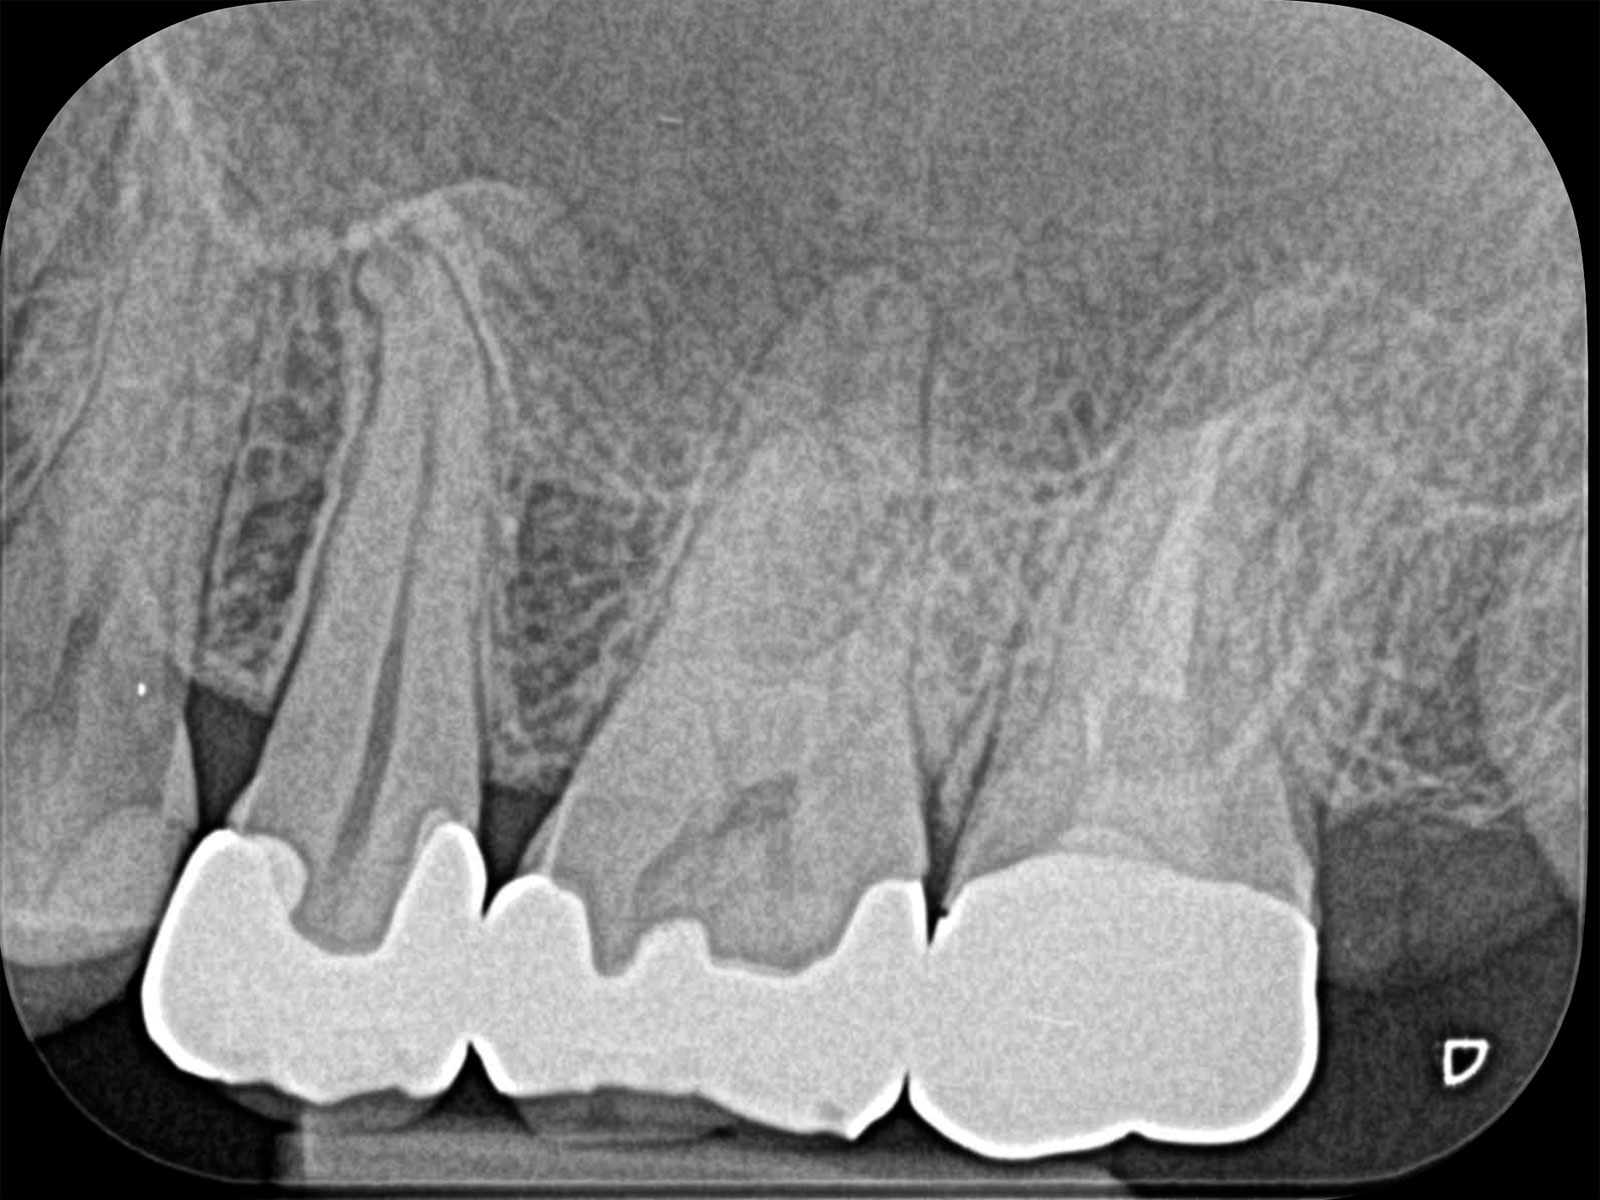

以下が実際に当院で処置した症例です。根管治療で痛みが再発する原因は、細菌が引き起こす炎症です。増殖した細菌が根の先まで進行し、膿がたまります(根尖病巣)。治療後は黒い影がなくなっていることがわかります。

また、治療精度が向上することで、結果的に患者さんの来院回数を減らすことも可能です。